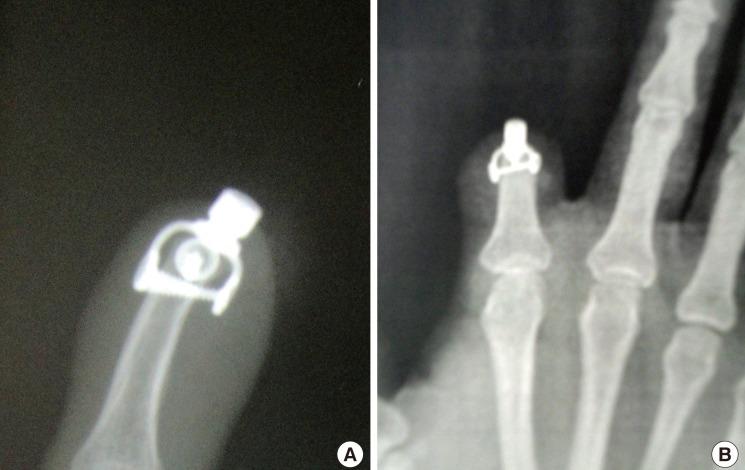

Osseointegrated Finger Prostheses Using a Tripod Titanium Mini-Plate.

Digital amputation is a common upper extremity injury and can cause significant impairment in hand function, as well as psychosocial stigma. Currently, the gold standard for the reconstruction of such injuries involves autologous reconstruction. However, when this or other autologous options are not available, prosthetic reconstruction can provide a functionally and aesthetically viable alternative. This study describes a novel technique, known as a tripod titanium mini-plate, for osseointegrated digit prostheses, and reviews the outcomes in a set of consecutive patients.

Seven patients were included in this study. Their average age was 29 years. Five patients had single-digit amputations and 2 patients had multiple-digit amputations. Functional and aesthetic outcomes were assessed using the Q-DASH score (average, 10.4) and VAS score (average, 9.1), respectively. One episode of mild cellulitis was seen at 24 months of follow-up. However, it was treated successfully with oral antibiotics. No other complications were reported.